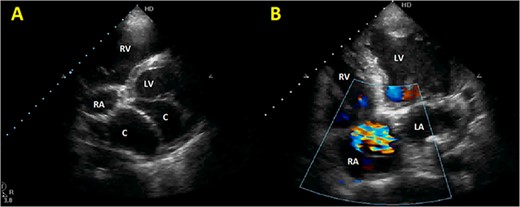

Initial physical examination showed stable vital signs. Auscultation found systolic murmurs of mitral and tricuspid regurgitations. There were no peripheral edema or other signs of heart failure. Abdominal examination revealed no tenderness, hepatomegaly or ascites. Electrocardiogram at admission showed sinus rhythm with no conduction abnormalities or signs of ischemia. Chest radiograph found an enlargement of the cardiac silhouette. Routine blood tests were normal. Transthoracic echocardiography (TTE) found a bi-atrial cystic structure, which we initially suspected to be a hydatid cyst as cystic echinococcosis is highly endemic in Morocco. Color Doppler showed a massive shunt with blood coming into the right atrium (RA) from an unknown source (Fig. 1). Cardiac magnetic resonance imaging (CMR) showed a bilobed cystic lesion hypointense on T1 and T2 sequences, with the same signal as cardiac chambers, located below and behind the left atrium (LA). The superior lobe was 48-mm wide and the inferior lobe 65-mm wide. On the peripheral wall of this structure, a giant circumflex artery (LCX), with a right atrial shunt, was present (Fig. 2). Coronary angiography (CA) along with computed tomography angiography (CCTA) confirmed the bilobed circumflex saccular aneurysm and CAF (Figs 3 and 4).

Initial TTE. (A) Parasternal short-axis view showing a bi-atrial cystic lesion; (B) apical 4-chamber view showing color Doppler aliasing in the RA, indicating a shunt. RV, right ventricle; LV, left ventricle; C, cystic lesion.